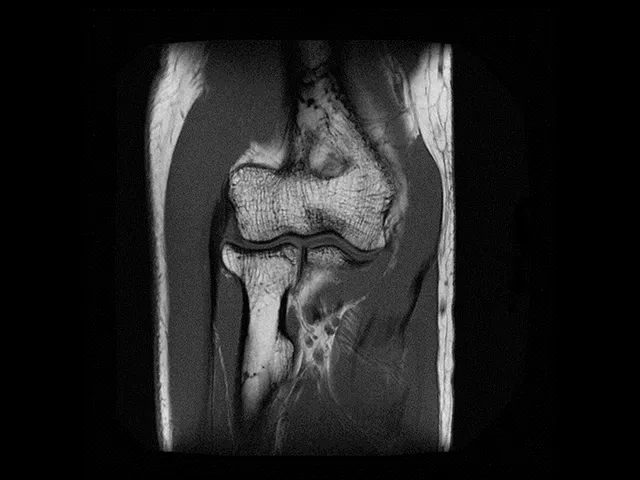

The purpose of this musculoskeletal MRI course is to learn about different topics in MSK radiology through a five-day long programme based on multiple lectures, daily reporting from individual work stations on specific teaching cases with subsequent group discussion. A successful fellowship will provide you with knowledge that can help you address ongoing clinical challenges, as well as future pursuits.

This week-long MSK fellowship includes an overview of the most common joints in practice with a daily presentation, individual case readings from the TMC Academy teaching file with group-based case read-outs. Standard reporting templates are used in order to help you navigate and write high-quality reports. Tailored programmes can be offered if requested well in advance.

At the end of the programme you will be able to comfortably identify and report on common pathology seen in daily practice, including in the sports field.